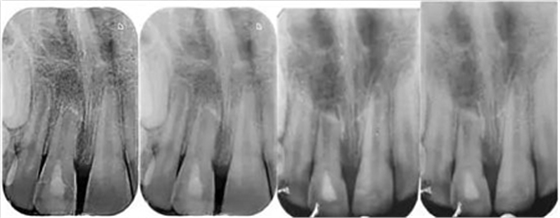

影像學(xué)檢查:根尖片以及全景片(圖2)提示牙槽骨骨折,根尖挫入至唇側(cè)骨板或鼻底。根尖片提示牙11,12 和21根尖發(fā)育不完全,呈喇叭口狀。受累牙的根管壁薄且不完全成形(圖2)。牙片顯示沒(méi)有冠折和根折。

診斷:牙11嚴(yán)重挫入,牙12中度挫入,牙21震蕩傷。

( 圖2)